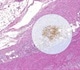

An application example is the evaluation of the HER2 status of breast cancer patients. Typically the pathological scoring of the HER2 status in breast cancer is either based on immunohistochemical IHC staining to mark the HER2 protein on the cell membrane, or on FISH to mark the HER2 ribonucleic acid (RNA) that contains the genetic information to produce the HER2 protein. By using the aligned images the scoring of HER2 protein overexpression and gene amplification could be combined to achieve a higher precision.